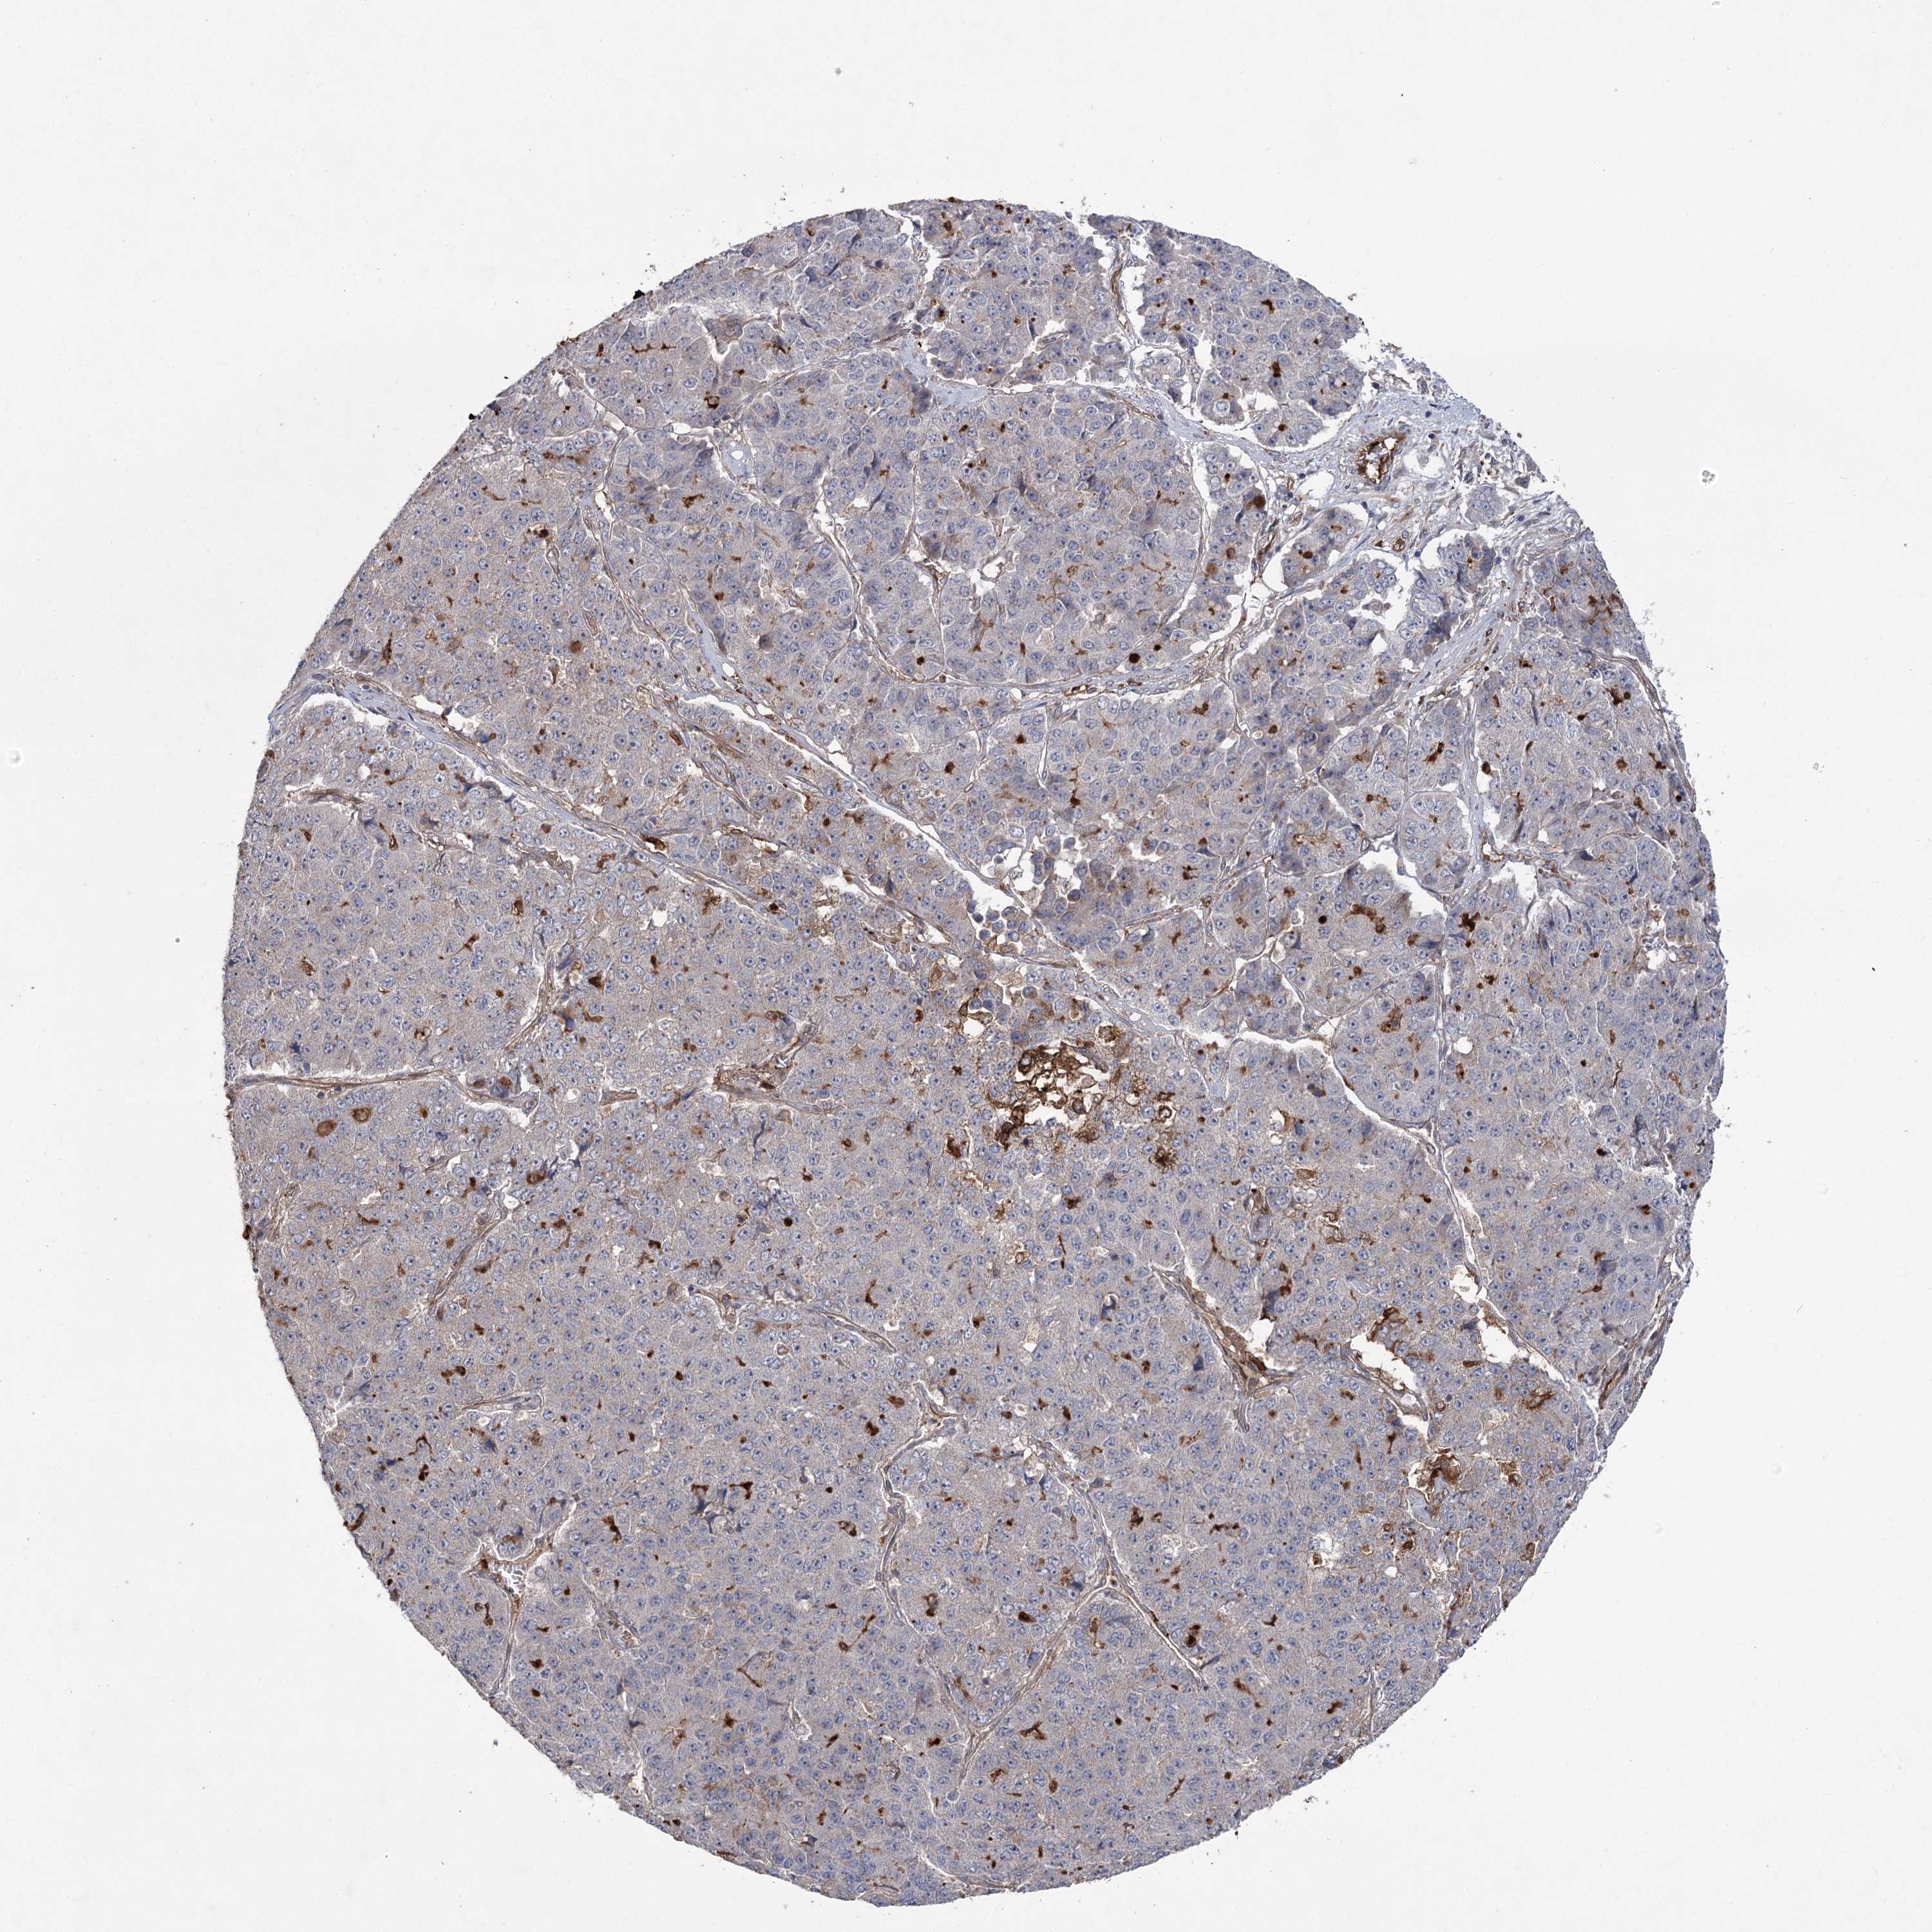

PANCREATIC CANCER - Protein expressioni

A mouse-over function shows sample information and annotation data. Click on an image to view it in a full screen mode. Samples can be filtered based on level of antibody staining by selecting one or several of the following categories: high, medium, low and not detected. The assay and annotation is described here.

Note that samples used for immunohistochemistry by the Human Protein Atlas do not correspond to samples in the TCGA dataset.

Antibody stainingi

Antibody staining in the annotated cell types in the current human tissue is reported as not detected, low, medium, or high, based on conventional immunohistochemistry profiling in selected tissues. This score is based on the combination of the staining intensity and fraction of stained cells.

Each image is clickable and will lead to virtual microscopy that enables deeper exploration of all samples and also displays staining intensity scores, fraction scores and subcellular localization as well as patient and tissue information for each sample.

Antibody HPA038504

Staining

High

Medium

Low

Not detected

Intensity

Strong

Moderate

Weak

Negative

Quantity

>75%

75%-25%

<25%

None

Location

Nuclear

Cytoplasmic/membranous

Cytoplasmic/membranous,nuclear

Adenocarcinoma, NOS